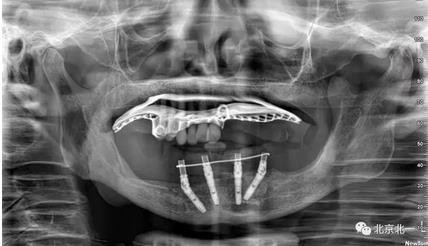

術(shù)前導(dǎo)板設(shè)計(jì),CBCT掃描,制作定位導(dǎo)板1

制作第二副備洞導(dǎo)板, 和第一幅是不同的。